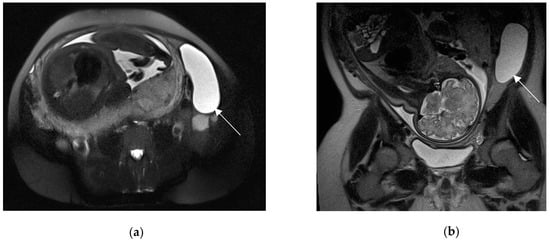

Figure 1.

Acute appendicitis in a 29-year-old woman with fever and acute abdominal pain. US shows thick-walled (maximum thickness 3.4 mm as indicated in (a)), and dilated tubular structure, containing hyperechoic spots (appendicoliths) (b). Periappendiceal fluid is also depicted.